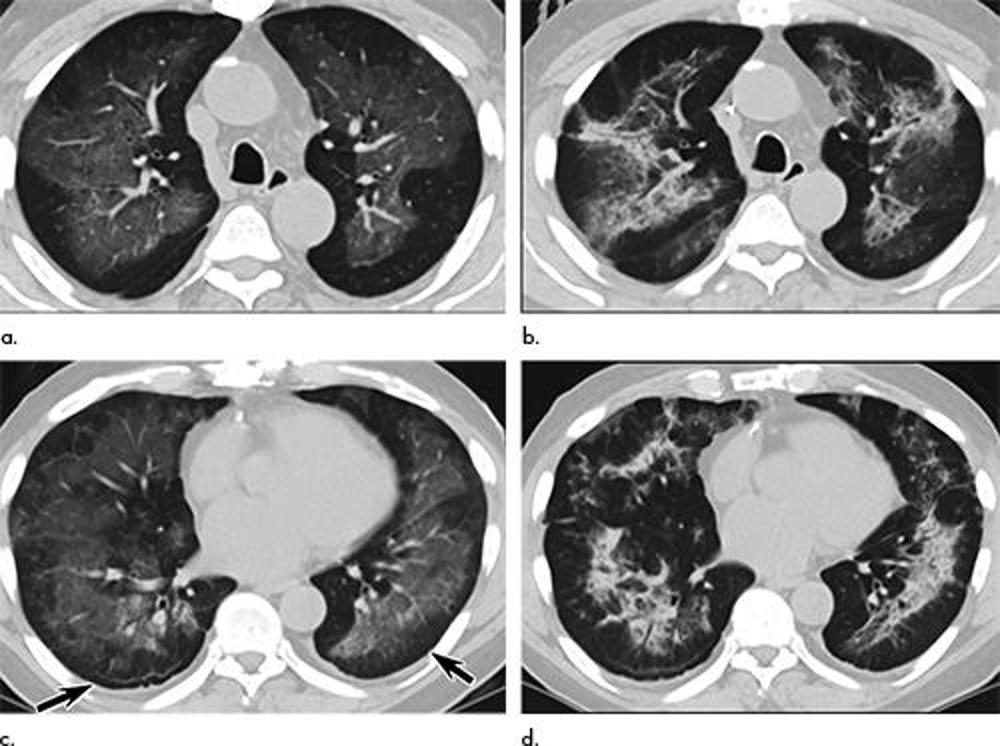

Figure 5. Images in a 39-year-old man with respiratory failure hospitalized for 10 days with an electronic cigarette or vaping product use–associated lung injury manifesting as an acute lung injury pattern at CT with some CT features suggesting a hypersensitivity pattern. (a, b) Axial enhanced CT images through the (a) mid and (b) lower lungs at presentation show multifocal areas of ground-glass opacity with prominent lobular low attenuation in the bases (arrows) suggesting small airway obstruction in addition to the ground-glass opacity. (c, d) Axial unenhanced CT images through the (c) mid and (d) lower lungs obtained 64 days after presentation show complete clearing of lung parenchymal abnormalities. Right middle lobe opacity (c) reflects site of surgical lung biopsy, which showed acute lung injury with organization, but no granulomas or other features typical of hypersensitivity pneumonitis.